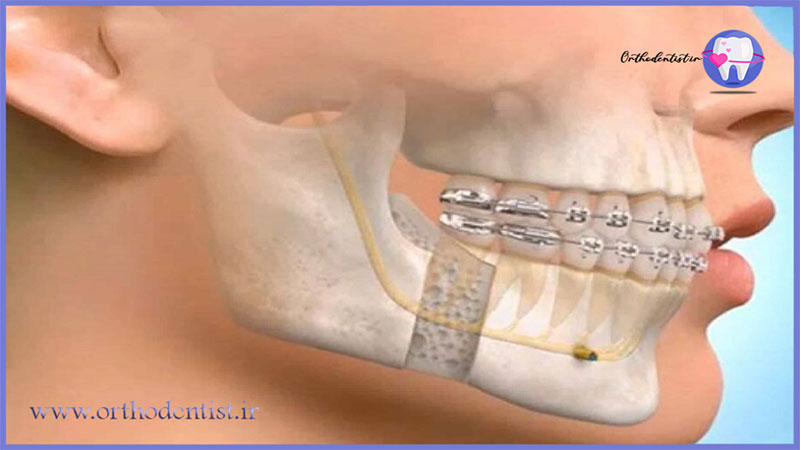

- براکتهای ثابت (معمولی): ارتودنسی ثابت معمولی شامل نصب براکتها بر روی سطح دندانها است که با استفاده از سیمهای فلزی یا شفاف، دندانها را به موقعیت مطلوب کشیده و تصحیح میکند.

- جراحی ارتودنسی: برای مواردی که نیاز به تغییرات بزرگتر در فرم یا موقعیت فکها وجود دارد، جراحی ارتودنسی ممکن است لازم باشد. این روش شامل ترکیبی از ارتودنسی و جراحی فک است.